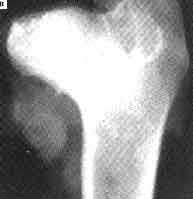

Radiographic (X ray) signs of Legg Perthes are usually gross and discouraging, since many cases are not referred to the vet or the specialist for diagnosis until the dog has been limping for a long time or the disease has progressed to the point that it becomes a more real problem to the owner. These small dogs put so little weight on their tiny hip joints that they almost can compensate for discomfort by “walking on their forelimbs instead of their four limbs.” Many are “couch potatoes” or spend much time being carried, but even then, picking up an affected dog in a certain manner can put more pressure on the joint than normal locomotion, so pain at that time is often the stimulus to do something about it. Owners and vets have reported “incredible pain” and constant, progressive discomfort, inability to stay long in any one position, and bone lysis (loss through a process akin to dissolving or consuming) at other areas in the limb distal (further away, the opposite of proximal) to the hip.

These are similar to those in LCPD. The earliest radiographic signs of LCPD, should you look for them before they change, include an increased radiodensity (opacity as seen on the radiograph) in the lateral part of the epiphysis of the femoral head. Lateral means the part away from the mid-line or medial; the “outside.” Resorption of necrotic (dying, rotting or decomposing) trabecular bone cells is next, accompanied by a lysis (dissolving or being consumed) of bone. These are replacement attempts by the body, similar to the attempt to replace bone that takes place during HD remodeling; eventually there is fracture or collapse, like a frame house riddled by termites. As HD may or may not be concurrent, the congruity of the ball and socket coxofemoral joint might still be maintained until collapse.

| Legg-Perthes is mostly found in Toy breeds. | Legg-Perthes; showing necrotic femoral head | Legg-Perthes necrosis with HD |